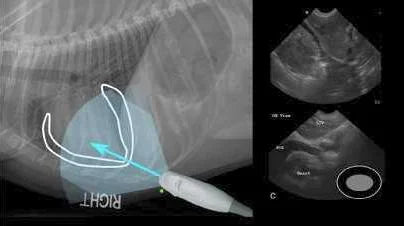

O protocolo Global FAST facilita a detecção rápida e não invasiva desses fluidos, utilizando pontos-chave de ultrassom para examinar as cavidades abdominal, torácica e cardíaca em busca de acúmulo de fluido ou sinais de trauma. Graças ao ultrassom, os veterinários podem detectar a presença de ascite e derrame pericárdico em estágios iniciais, possibilitando intervenções imediatas e potencialmente salvadoras de vidas.

O uso do protocolo Global FAST permite que os veterinários identifiquem rapidamente o quantidade e localização do líquido pericárdico , avaliando se é necessária intervenção de emergência, como uma pericardiocentese guiada por ultrassom .